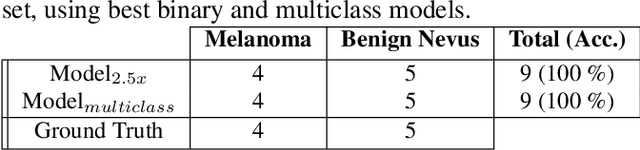

Detection and Localization of Melanoma Skin Cancer in Histopathological Whole Slide Images

Feb 06, 2023

Melanoma diagnosed and treated in its early stages can increase the survival rate. A projected increase in skin cancer incidents and a dearth of dermatopathologists have emphasized the need for computational pathology (CPATH) systems. CPATH systems with deep learning (DL) models have the potential to identify the presence of melanoma by exploiting underlying morphological and cellular features. This paper proposes a DL method to detect melanoma and distinguish between normal skin and benign/malignant melanocytic lesions in Whole Slide Images (WSI). Our method detects lesions with high accuracy and localizes them on a WSI to identify potential regions of interest for pathologists. Interestingly, our DL method relies on using a single CNN network to create localization maps first and use them to perform slide-level predictions to determine patients who have melanoma. Our best model provides favorable patch-wise classification results with a 0.992 F1 score and 0.99 sensitivity on unseen data.